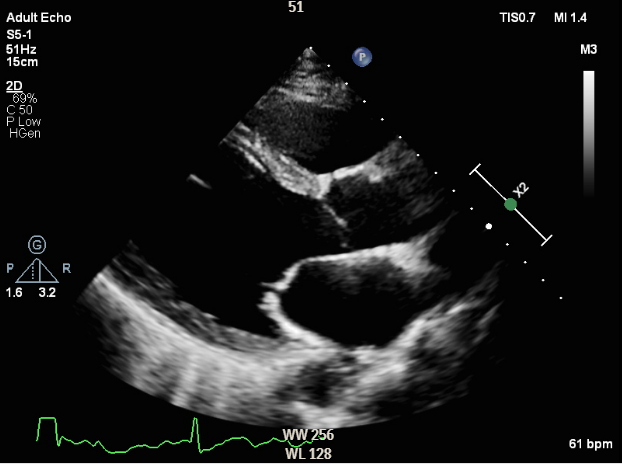

Relevant Test Results Prior to Catheterization

Electrocardiography showed normal sinus rhythm with left ventricular hypertrophy. Chest X-ray revealed borderline cardiomegaly and prominent pulmonary vasculature. Transthoracic echocardiography demonstrated a dilated left ventricle with a severely reduced ejection fraction of 32.7%. Laboratory tests showed elevated NT-proBNP (351.2 pg/mL), normal blood counts, preserved renal and hepatic function, and HbA1c of 6.1%.